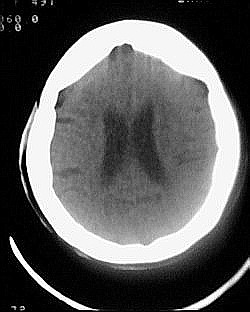

患者/49y/ 女/4年前有脑梗, 现因右侧肢体无力来院做ct扫描 ! 老师们看看这骨头有事吗?钙化点是什么原因呀??

1.颅骨对称性、形态规整性增厚,应属发育异常。四叠体池左后侧单发点状钙化,无其他阳性表现,多属正常,不需要过多关注。

2.双侧基底节区域多发性梗塞灶。

1、多发腔隙性脑梗塞是肯定的了。

2、颅骨形态规整性的增厚,密度增高,有无骨髓方面的疾病,建议骨髓穿刺。

不除外发育变异哈。

1.双侧基底节区腔梗。

2.颅骨内外板广泛性增厚,板障狭窄甚至消失,双侧对称。无明显相应临床症状。考虑“泛发性骨皮质增厚症”。可进一步检查下颌骨及管状骨骨干。(下颌骨骨小梁增多、密集,密度增高亦为本病特点,管状骨骨干皮质向内增厚引起骨皮质厚度增加,骨密度增浓、髓腔狭窄但不消失,骨干周径较少增加)。与石骨症鉴别,后者很少影响颅盖骨和下颌骨,管状骨改变主要累及干骺端和骨骺,而骨干皮质较少增厚,椎体和髂骨翼有特征性表现。